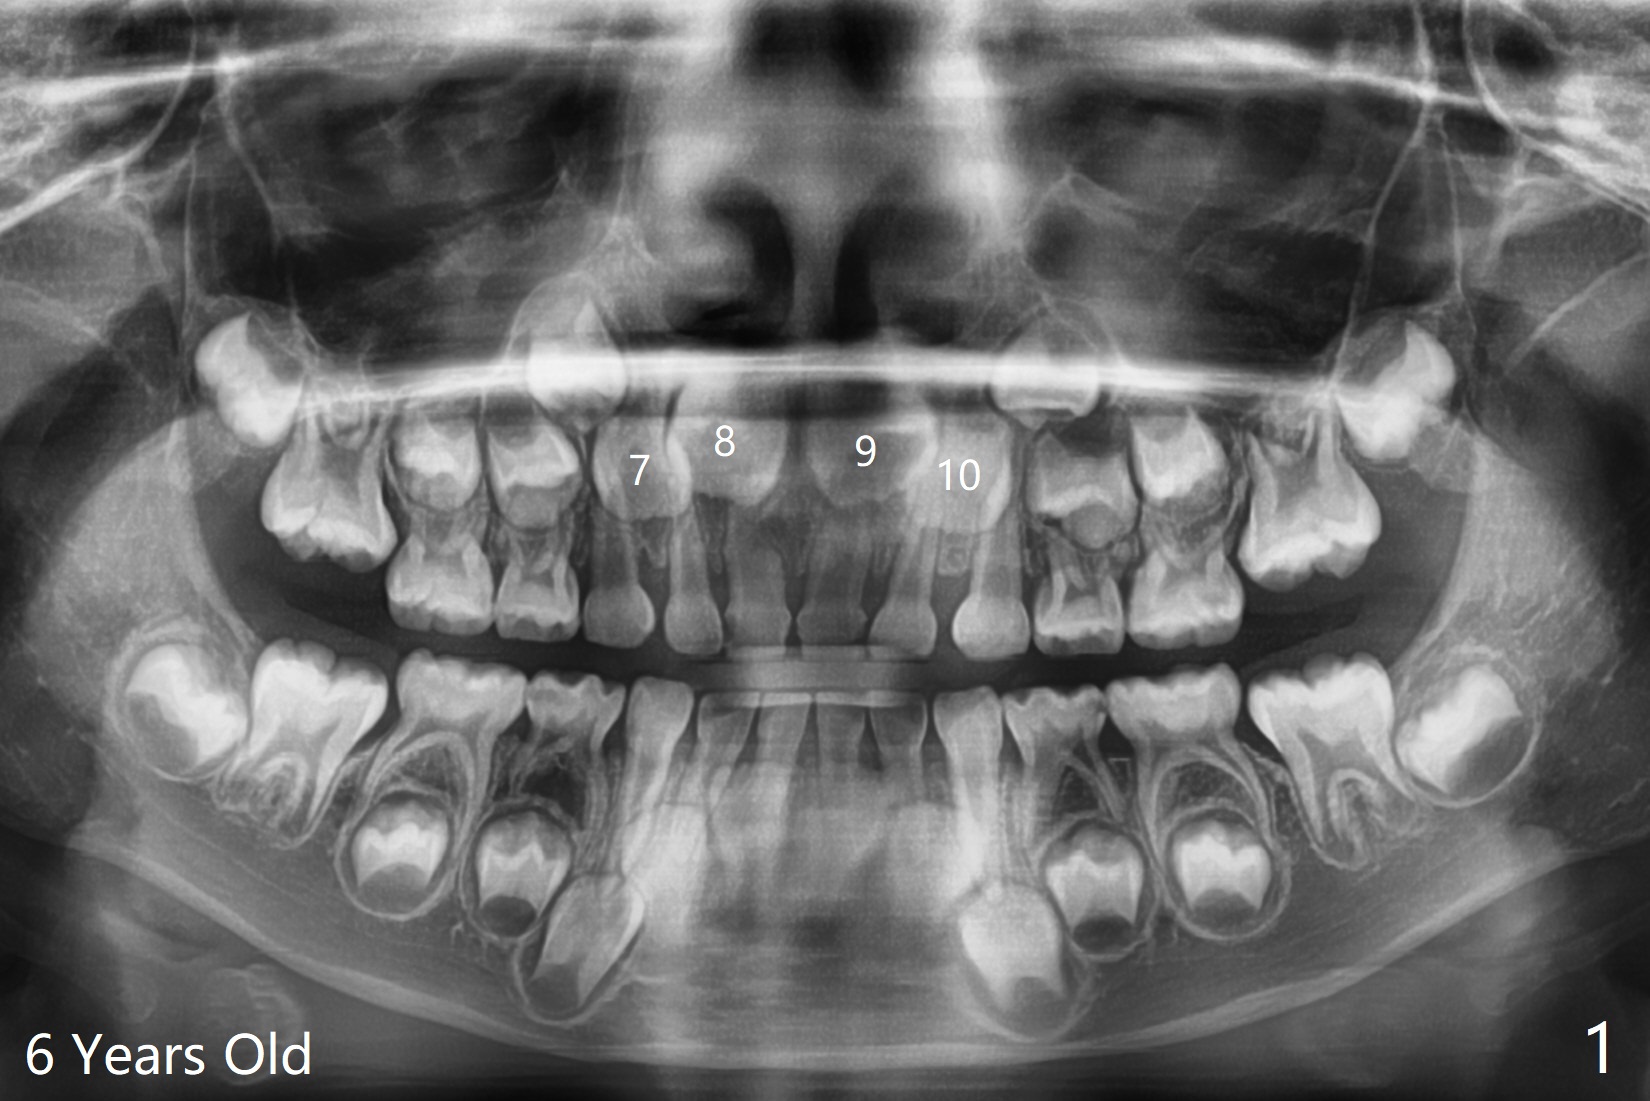

6岁女孩上中切牙发育萌出好像比侧切牙晚(图一),七岁时萌出顺序正常(图二),但是八岁时右上中切牙阻生(图三,四)。似乎拥挤是阻生原因,除了切开助萌之外,扩弓是必要的。不过她口腔卫生欠佳。